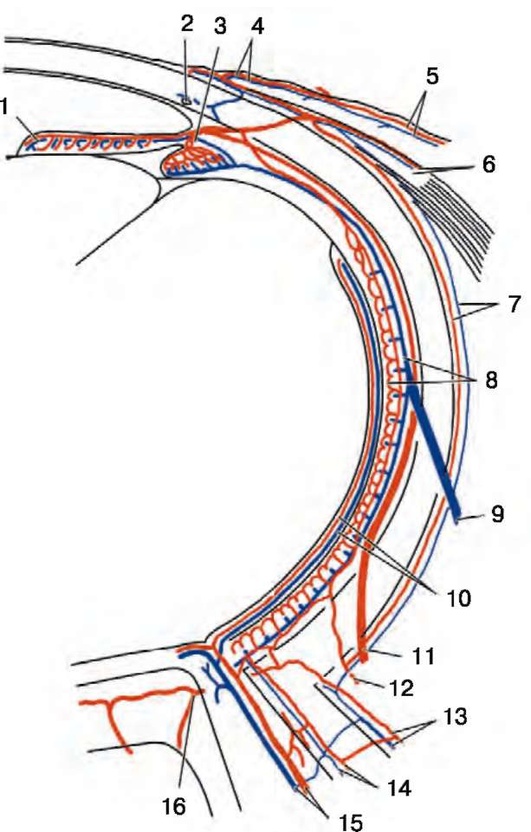

Рис. 2.2. Ретробульбарный отдел зрительного нерва и его кровоснабжение: 1 - сетчатка; 2 - хориоидея; 3 - склера; 4 - задняя короткая цилиарная артерия; 5 - твердая мозговая оболочка; 6 - мягкая мозговая оболочка; 7 - зрительное отверстие; 8 - глазная артерия; 9 - пиальное сплетение; 10 - центральная артерия сетчатки; 11 - ветвь центральной артерии сетчатки к стволу зрительного нерва; 12 - сечение галлерова или циннова артериального круга; 13 - нижняя папиллярная артерия; 14 - верхняя папиллярная артерия (по Wolff, 1948)